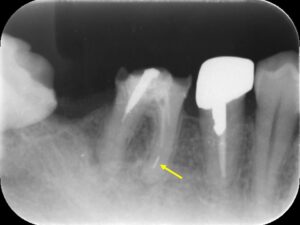

初診時レントゲン。右側下顎第一大臼歯の被せ物(クラウン)は外れており、虫歯と根尖病巣を認める。近心根にはファイル破折片を認める(矢印)。根尖病巣を認めるため、可能であれば破折ファイルを取り除きたいケース。